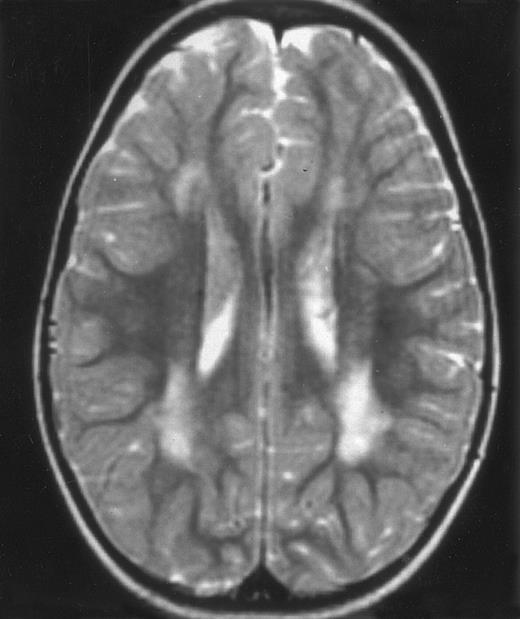

Nine patients were transplanted soon after the remission of initial CNS and systemic manifestations. All of these patients had meningitis only as the CNS manifestation. The median delay between diagnosis and BMT was 4 months (range, 2 to 14 months). Two patients died of BMT-related toxicity (both recipients of an HLA-identical BMT). Seven patients are alive and well with normal neurological examination, normal CSF tap, and normal cognitive development after a follow-up of 18 to 132 months (median, 55 months) (four recipients of an identical BMT and three of a partially-identical BMT). After BMT, chimerism studies demonstrated full or partial engraftment in all of these seven patients. MRI was performed before and after the transplantation in three cases. Two patients had a normal MRI or an isolated subarachnoidal and subdural space dilatation before transplantation and a normal MRI, respectively 4 years and 18 months after transplantation. One patient had white matter abnormalities before transplantation, which remained identical 2 years after transplantation (Fig 4).

MRI of a symptom-free 31/2-year-old child who received BMT at 18 months showing the persistent white matter abnormalities.

The efficiency of allogenic BMT in preventing relapses of peripheral HLH manifestations has already been reported, including by our group.13,27,28 In this study, we describe the remarkable effect of BMT on the prevention of subsequent neurological manifestations and the good cognitive and neurological evolution of the seven transplanted children who are long-term survivors. In addition, brain imaging performed several months or years after BMT showed a normal aspect or a stabilization of white matter abnormalities. These seven patients had initial meningitis, but never developed neurological symptoms before BMT. Therefore, this study does not allow conclusions on the potential beneficial effects of BMT in patients with neurological symptoms. Nevertheless, it is likely that when atrophy and/or necrotic lesions are present, BMT could probably, at best, lead to stabilization of lesions carrying a risk of neurological and cognitive sequelae. We, therefore, believe that the optimal strategy for the treatment of HLH patients is to perform a BMT as early as possible once complete (systemic and neurological) remission has been achieved. Today, BMT from alternative donors, ie, matched unrelated29 and haplo-identical related donors (Jabado et al submitted), can also be considered. However, this approach raises the question of the accuracy of HLH diagnosis in patients without a family history or consanguinity. In this setting, it may be more appropriate to wait until relapse to confirm the HLH diagnosis, although the risk of severe CNS lesion occurring in the meantime is significant.